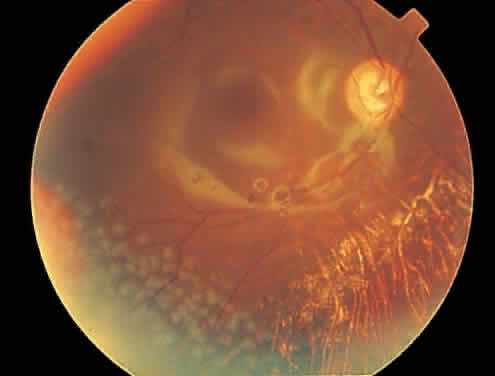

Rhegmatogenous retinal detachment occurs in 10% to 20% of eyes with CMV retinitis.37–39 However, before the AIDS epidemic, there were only five reported cases of this association.10,40 In patients living more than 1 year with CMV retinitis, risk of retinal detachment may be as high as 50%,41 which increases if more than 25% of peripheral retina is involved by disease.41,42 Retinal breaks in eyes with CMV retinitis typically occur within or at the border of necrotic atrophic retina (Fig. 6).43 The ensuing retinal detachments are typically difficult to repair with standard scleral buckling procedures. This is because of the location and number of retinal breaks, the difficulty in visualizing all breaks in necrotic retina, and the high incidence of associated proliferative vitreoretinopathy. In many cases, pars plana vitrectomy and retinal tamponade with silicone oil or long-acting intraocular gas is indicated (Figs. 7 and 8).37,44,45 However, scleral buckling may be considered in small peripheral retinal detachments when the entire involved area can be completely placed on the element. Laser photocoagulation demarcation has also been described to delimit macula-sparing CMV-related retinal detachment.46 Although anatomic success of macular reattachment with surgery is high, the visual results are often limited by the underlying disease process.47 When considering surgical repair of CMV-induced retinal detachment, consideration should be given to the potential for ambulatory vision, the patient's systemic condition and the status of the fellow eye.

Fig. 6. A shallow cytomegalovirus-related retinal detachment is present inferiorly and involves the fovea.

Fig. 7. Repair of the eye in color plate H with silicone oil. Note the silicone oil reflections in the macula.